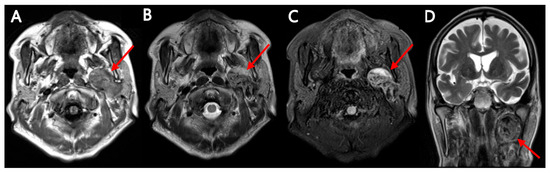

Background: The purpose of this study was to examine the relationship between qualitative characteristics and quantitative parameters from contrast-enhanced ultrasound (CEUS) and microvessel density (MVD) in hepatoblastoma (HB), as well as to investi...